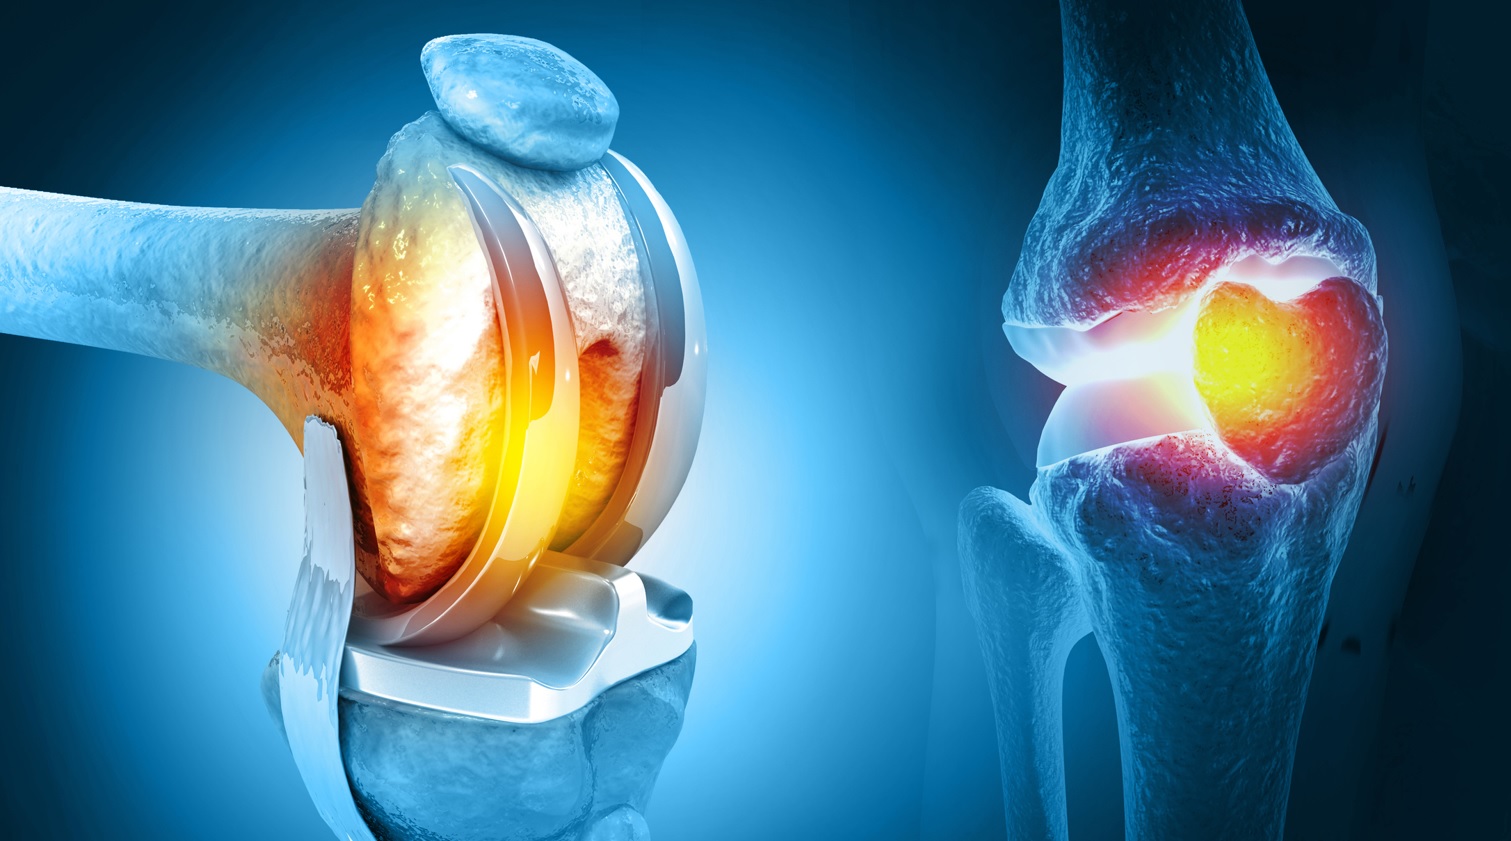

Примеры протезов коленных суставов Zimmer

Раздел: Образы вокруг